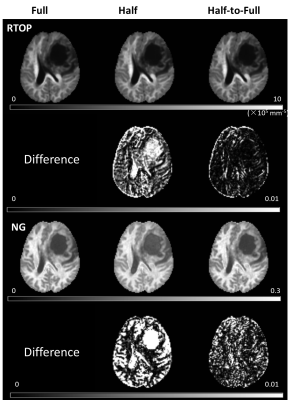

The half q-space under-sampling scheme did not significant sacrifice the accuracy of quantitative maps of advanced diffusion model but could accelerate the acquisition by 2 fold. In addition, a symmetrically data copy step is needed to improve the estimation accuracy.

Figure 2. RTAP and NG maps (MAP-MRI model) of three different schemes (Full, Half and Half-to-Full) and their corresponding percent of square coefficient of variation (CV) for a patient.